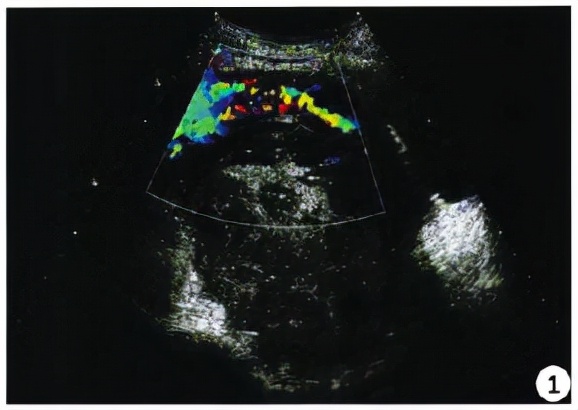

护士姐姐带着女生去完善β-HCG和超声检查,两项检查结果均明确提示宫外孕。

超声检查结果

如果患者β-HCG大于2000MIU/L,可采用阴道超声进行检查,如未发现患者孕囊,基本可确诊为异位妊娠。

宫外孕图示